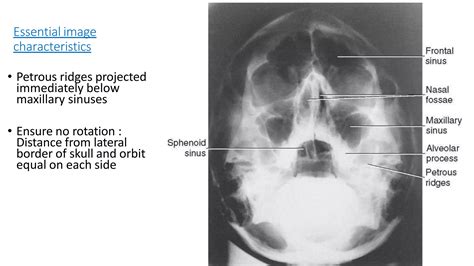

Understanding the anatomy of the sinuses through an X Ray Sinuses Labelled image is crucial for diagnosing and treating various sinus-related conditions. Sinuses are air-filled cavities within the bones of the face and skull, and they play a significant role in respiratory function, voice resonance, and immune defense. This post will delve into the intricacies of sinus anatomy, the importance of X-ray imaging in diagnosing sinus issues, and how to interpret an X Ray Sinuses Labelled image effectively.

Interpreting an X Ray Sinuses Labelled Image

Interpreting an X Ray Sinuses Labelled image requires a basic understanding of sinus anatomy and the ability to recognize common abnormalities. Here are some key points to consider:

Normal Sinus Appearance

In a normal X Ray Sinuses Labelled image, the sinus cavities appear as dark, air-filled spaces surrounded by bony structures. The mucosa lining the sinuses should be thin and uniform, with no signs of thickening or fluid accumulation.